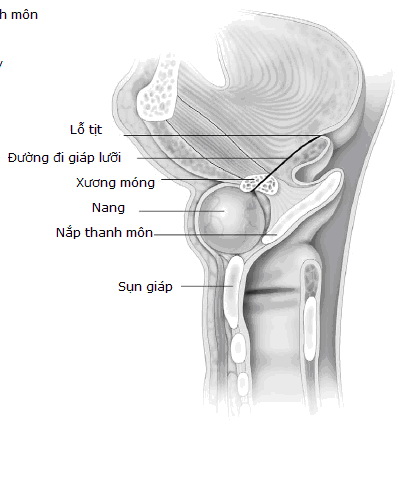

Xương của chúng ta là một mô liên kết đặc biệt bao gồm các tế bào và chất khuôn xương, trong đó chất khuôn xương bao gồm các sợi collagen và các mô liên kết khác giàu chất glucoaminoglycin. Trong bệnh tạo xương bất toàn, do tổn thương các gen chỉ huy sản xuất collagen type 1 nên số lượng hoặc chất lượng của các sợi collagen bị giảm sút làm cho xương giảm khả năng chịu lực, bị biến dạng và dễ gãy. Do vậy khi bị bệnh thì xương không có độ bền dẻo nữa mà lại giòn và vì thế mà xương rất dễ biến dạng và gãy ngay khi không có sang chấn hoặc sang chấn rất nhẹ như ho, hắt hơi, vỗ vai....Cũng vì thế mà còn gọi nôm na là "xương thuỷ tinh" để chỉ bệnh này.

Collagen còn là thành phần chính của nhiều mô liên kết nên bệnh cảnh lâm sàng không chỉ ở xương mà còn ở nhiều cơ quan khác như da, dây chằng, củng mạc mắt, răng như: như: gãy xương tự phát, biến dạng xương, lùn, bất thường của răng (tạo răng bất toàn), giảm thính lực, củng mạc mắt có màu xanh.